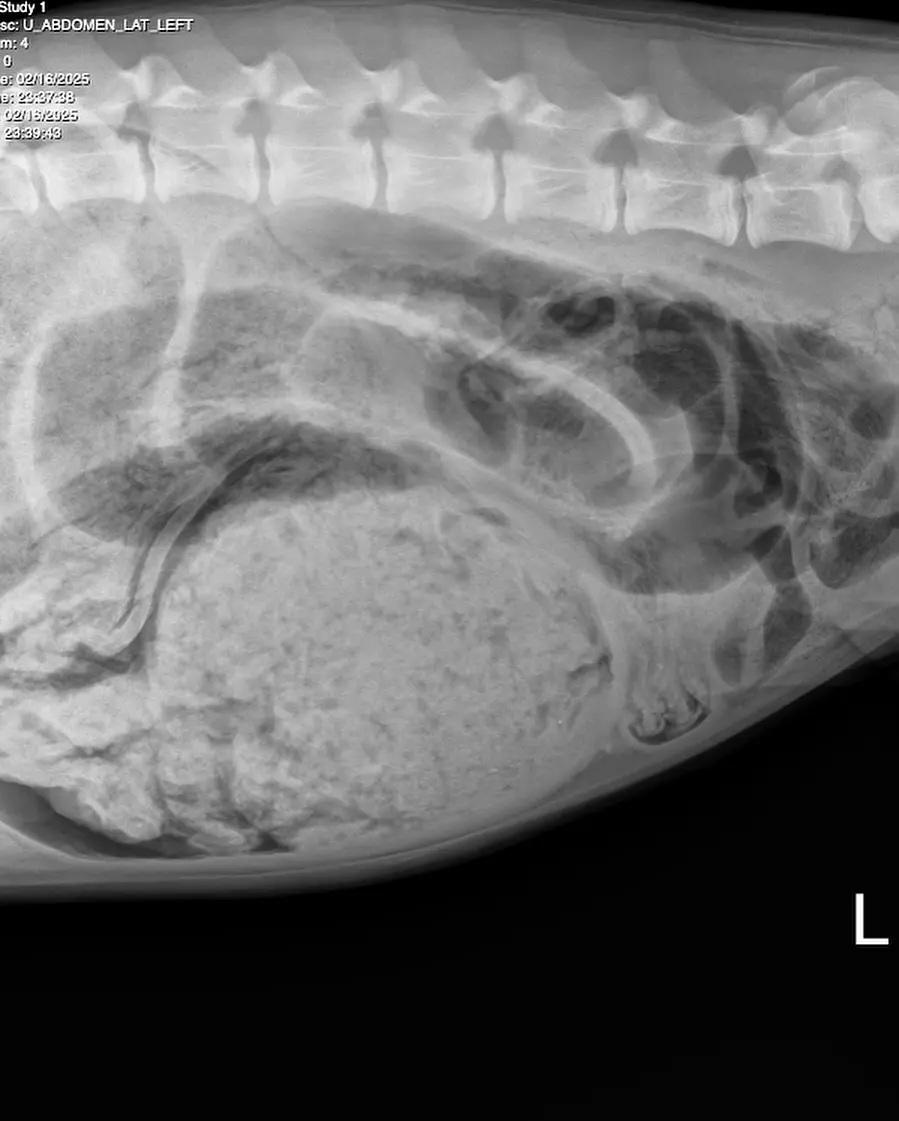

7個月大的Luna肚裡塞滿東西。(互聯網)

醫生為愛食衣物的Luna做開肚手術,清理其胃裡的襪子等異物,還有切開腸臟拿出阻塞腸道的連身衣。動物急症中心在上社交網展示從Luna肚子取出的襪子,各式各樣長短襪都有,還有牠的X光片,可見胃裡塞滿東西。Luna做手術取出肚裡異物後已恢復元氣,再次搖起尾巴。帖文提醒大家,若發現狗隻嘔吐、無力氣和肚部堅硬,應立即帶牠看醫生。